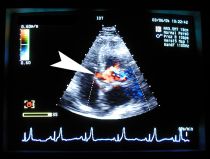

Zur genauen Diagnose der unterschiedlichen, bei Hund, Katze und Heimtieren vorkommenden, angeborenen und erworbenen Herzerkrankungen setzen wir verschiedene Ultraschalltechniken ein. Mit Hilfe von Ultraschallbildern können wir das Herz in der Bewegung von innen untersuchen und dabei die Herzklappen und die Herzmuskulatur in ihrer Form und ihrer Bewegung beurteilen. Wir setzen verschiedene Schallköpfe (3,5 -5 MHz und 7,5 MHz) ein und können dadurch auch bei kleinen Katzen, sowie Kaninchen und Meerschweinchen Untersuchungen durchführen. Zusätzlich zum normalen, sogenannten zweidimensionalen Ultraschall und der M-Mode Technik ist unser Ultraschallgerät mit der Dopplertechnologie (Farbdoppler, Schwarzweißdoppler und Gewebedoppler) ausgestattet, mit deren Hilfe wir den Fluss des Blutes durch die einzelnen Herzkammern sichtbar machen, die Geschwindigkeit und die Richtung dieses Blutflusses sowie die Kontraktionsbewegungen der einzelnen Herzmuskelbereiche messen. Dadurch können wir erstens die Art der Herzerkrankung, z.B. undichte Herzklappen (Mitral- bzw. Trikuspidalinsuffizienz, sogenanntes Altersherz), oder Verengungen der vom Herz abgehenden Arterien (Aortenstenose und Pulmonalstenose) diagnostizieren und zweitens deren Schweregrad genau erkennen.

Nur diese gründliche Abklärung versetzt uns in die Lage, für jeden Patienten die richtige Herztherapie auszuwählen. Im Einzelnen messen wir die Wandstärken der verschiedenen Herzmuskelanteile und die Größe der Herzvorhöfe sowie die Kontraktionskraft des Herzens. Wir beurteilen die Schlussfähigkeit der Herzklappen und messen den Rückfluss des Blutes (Reflux) über den undichten Herzklappen, bestimmen die Blutflussgeschwindigkeit über der Hauptschlagader (Aorta) und der Lungenarterie (Pulmonalarterie) und untersuchen die Herzscheidewand (Ventrikelseptum) und die Vorhofscheidewand (Vorhofseptum) auf angeborene Defekte.